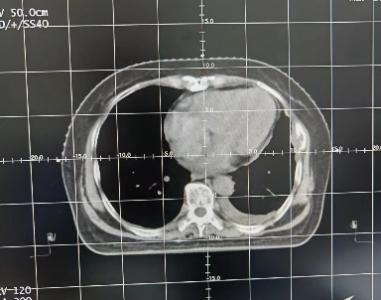

第三步:放疗CT定位

制定体膜后,患者需要移至放疗中心定位室,在佩戴体膜固定体位的前提下完成CT扫描。该CT扫描和在放射科完成的CT检查并不一样,生成的扫描图像将传输到医务人员使用的计划设计系统。医务人员会根据扫描图像勾画肿瘤和需要保护的器官,并进行剂量计算。因此,尽管部分患者此前可能进行了CT检查,但这一项模拟定位的CT扫描仍然必不可少。

扫描前治疗师会把患者体位固定好,然后进行CT扫描获取影像,从而确定肿瘤(靶区)和正常组织(危及器官)的位置,为接下来的靶区勾画和计划设计做准备。这步骤治疗师会在患者的体表皮肤或固定器具(真空垫或体膜 )上画各种标记线,其中,体表的标记线是进行身体再次固定的重要标志。需要注意的是,随着衣服摩擦或出汗等因素患者体表的标记可能会变得不清晰,因此需要仔细保护好。